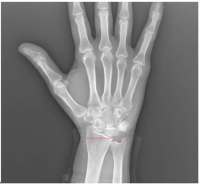

The radius and ulna are connected by the dorsal and volar radioulnar ligaments and are expected to be in a neutral position relative to each other within the wrist joint.[4] Ulnar variance is a term used to describe the positional relationship between the distal ulna and radius. Negative ulnar variance is the presence of the ulna 1 mm or more proximal to the radius and has been associated with conditions such as ulnar impingement syndrome, scapholunate dissociation, and Kienböck’s disease (Figure 1). Positive ulnar variance is the presence of the ulna 1 mm or more distal to the radius and is associated with conditions such as ulnar impaction syndrome, cartilaginous tears in the carpal bones, early degenerative changes, and triangular fibrocartilaginous complex (TFCC) tear (Figure 2).[5]

Hand and wrist radiographs were evaluated blindly by 2 rheumatologists (MP-SK). Hand radiographs were analyzed according to the Modified Sharp Score (MSS) system.7 The presence of any erosion or joint space narrowing (JSN) was used as a criterion to define “RA-type joint involvement (RJI).” “Severe joint involvement (SJI)” was defined as the presence of erosion with a score of 3 or higher or JSN with a score of 4 or more according to the MSS. Patients were also evaluated for ankylosis of any hand joint. Ulnar variance, as described by Hulten, was determined by measuring the distance between horizontal lines drawn at the subchondral bone of the distal radius, just beneath the articular cartilage, and the most distal subchondral border of the ulnar head.[8] A displacement of 1 mm or more of the ulna relative to the radius was defined as AUV. Radiographic evaluation was performed with full agreement; if there was disagreement between the readers, the X-ray was re-evaluated and an agreed final decision was made.

Ulnar variance defines the position of the ulna relative to the radius at the distal radioulnar joint, exhibiting increases during forearm pronation and decreases during supination.[9] Consequently, the standard approach commonly used to demonstrate ulnar variance is a method described in detail in Palmer’s study, which involves obtaining an X-ray with the shoulder abducted to 90 degrees, the elbow flexed to 90°, and the hand in a neutral position.[10] This method was used in the radiographs and evaluated the radiographs by measuring from the standard points defined by Hulten. Both methods have been shown to have high intraobserver and interobserver reliability in the literature.[9] In studies conducted on cadavers to assess ulnar variance, X-ray imaging was compared with dissection following the use of computed tomography (CT) and magnetic resonance imaging (MRI) techniques, leading to the conclusion that X-ray imaging may be sufficient for detecting ulnar variance.[10] Therefore, it was proposed that if routine X-ray imaging, commonly utilized in patients with RA, is performed using the Palmer method, both the disease findings and ulnar variance can be evaluated simultaneously without incurring additional costs.